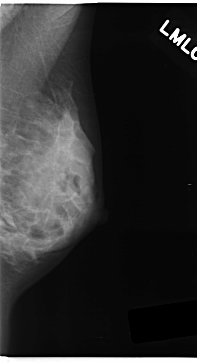

Digital Database for Screening Mammography

Volume: cancer_05 Case: C-0152-1

C_0152_1.LEFT_MLO

RIGHT_CC LINES 4776 PIXELS_PER_LINE 2528 BITS_PER_PIXEL 12 RESOLUTION 50 OVERLAY

RIGHT_MLO LINES 4720 PIXELS_PER_LINE 2384 BITS_PER_PIXEL 12 RESOLUTION 50 OVERLAY

FILE: C_0152_1.RIGHT_MLO.OVERLAY

TOTAL_ABNORMALITIES 1

ABNORMALITY 1

LESION_TYPE MASS SHAPE LOBULATED MARGINS ILL_DEFINED

ASSESSMENT 5

SUBTLETY 3

PATHOLOGY MALIGNANT